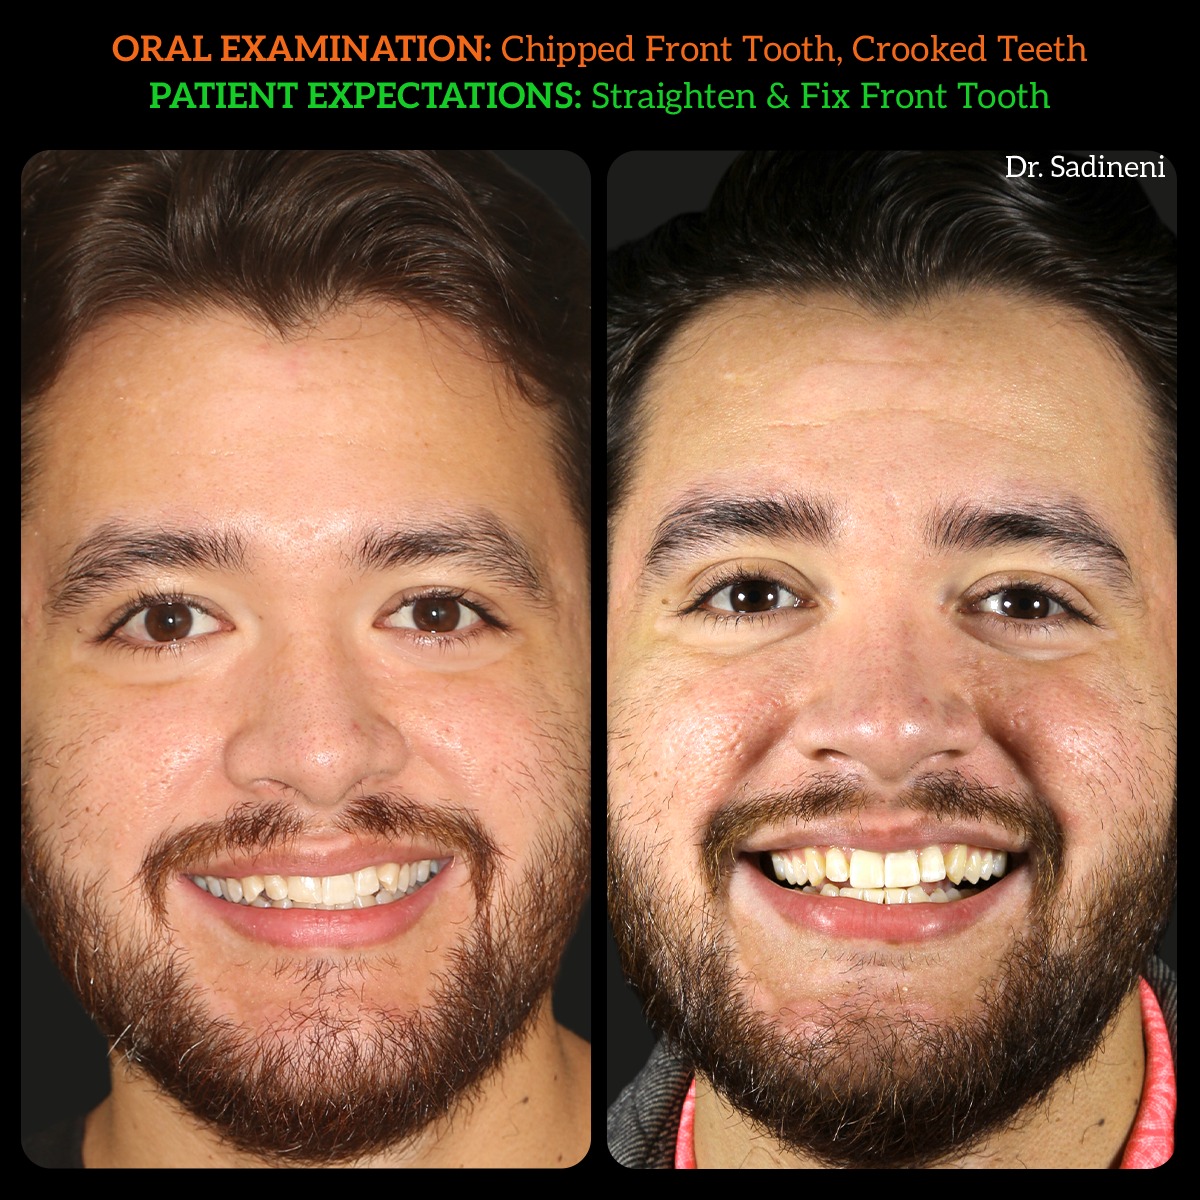

Jose Alacanter Invisalign bonding Transformation

patient concern: gaps and discoloration on front tooth